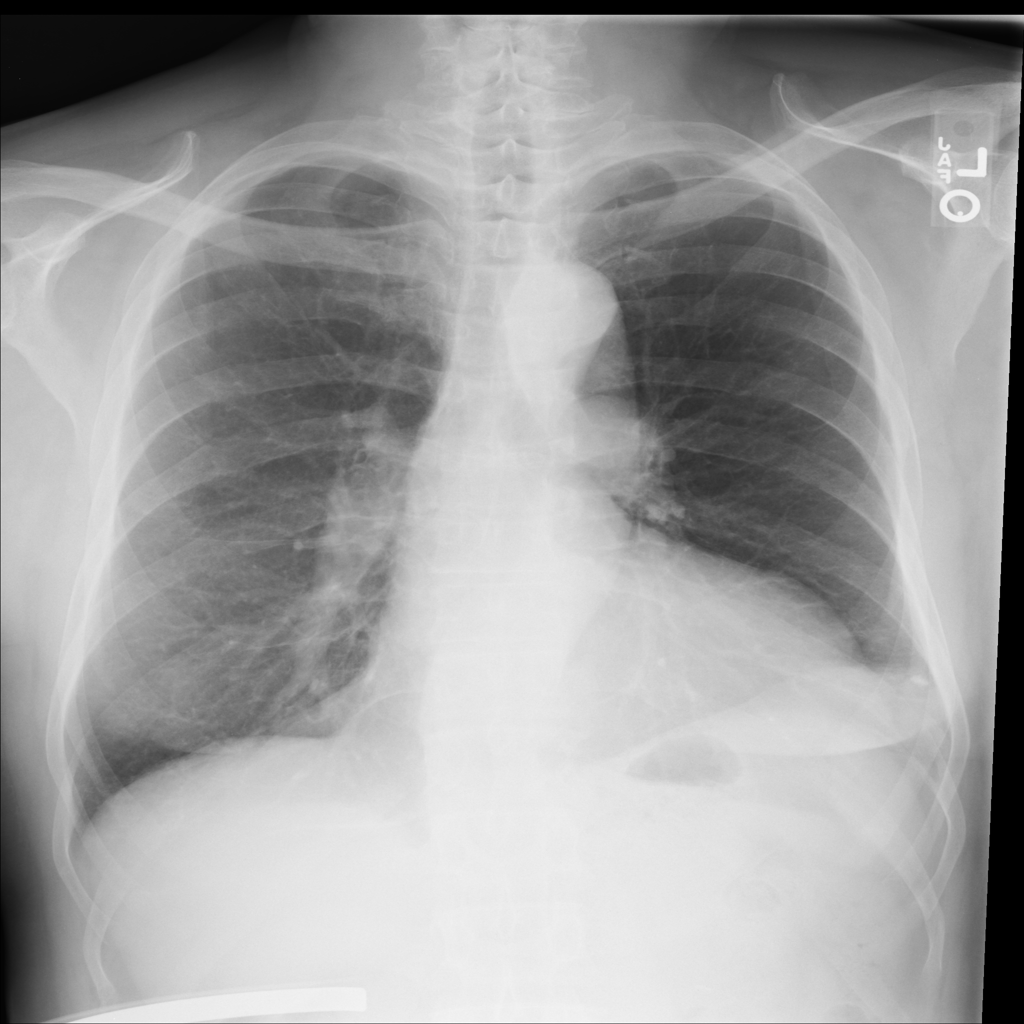

PAT-4639 · IMG-045Cardiomegaly

PAT-4639 · IMG-045

PA